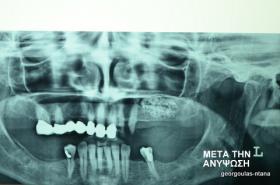

Στην ασθενή αυτή πραγματοποιήθηκε ανοικτή ανύψωση ιγμορείου άνω αριστερά. Σε πρώτη φάση πραγματοποιήθηκε η οστική αύξηση και 6 μήνες μετά τοποθετήθηκαν 3 εμφυτεύματα. Τόσο στην πανοραμική όσο και στην τομογραφία κωνικής δέσμης (CBCT) που πραγματοποιήθηκαν 6 μήνες μετά την ανύψωση είναι εμφανής ο σχηματισμός οστού. Η τελευταία ακτινογραφία και φωτογραφία λήφθηκαν 5 χρόνια μετά την προσθετική αποκατάσταση.